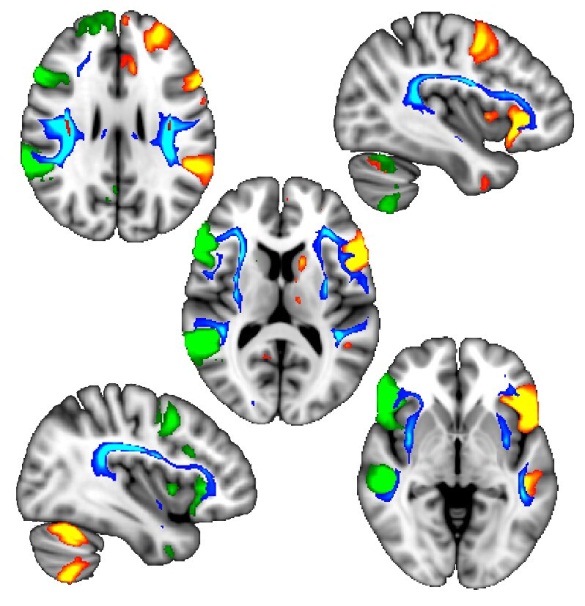

随后,他们对大约10000名参与者的详细脑成像结果发现,发现与左撇子相关的基因变异关联不同寻常的脑白质束,尤其是连接与语言功能关联大脑区域的脑白质束。

左脑两侧(绿色和橙色)的语言脑区域更协调,而且与左撇子相关的一个基因区域(蓝色)影响的脑白质束也连接在一起。图片来源:牛津大学。

牛津大学医学研究委员会研究员Akira Wiberg博士进行了分析,他说:“在左撇子参与者中,其大脑左右两侧的语言区域以更加协调的方式相互沟通。这为未来的研究提供了一个有趣的可能性:即左撇子在执行语言任务时可能更具有优势。当然,这些差异仅被视为对大量人群的平均值,而且并非所有左撇子都是通用的。”